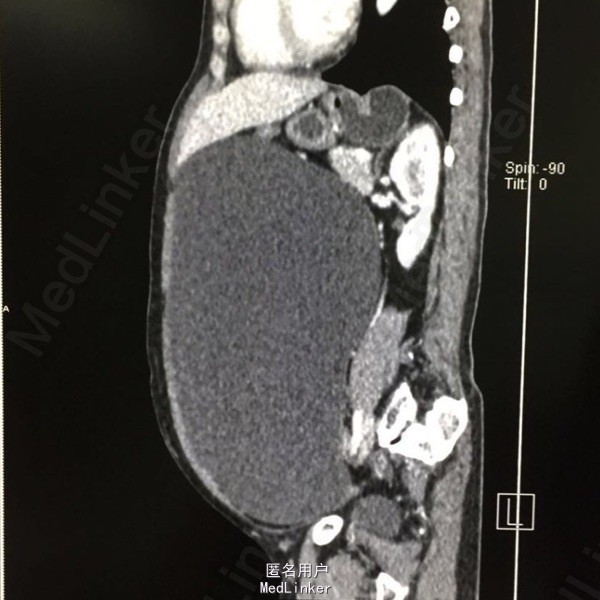

患者女性,54岁,因发现盆腔巨大包块半月余入院。半月前患者外院体检行B超提示腹部积水,遂至我院就诊。患者已绝经5年,有高血压病史5年,自诉血压控制可。

查体:腹部膨隆,可扪及一巨大包块,上至剑突,下达盆腔,双附件区触诊不满意。 辅查:我院腹部CT:盆腹腔可见一巨大囊性水样密度包块,大小约27.1×12.8cm,内未见分隔及壁结节影,考虑为右侧附件来源,囊腺瘤可能;子宫前壁肌瘤可能。

入院诊断:盆腔包块、子宫肌瘤。入院后完善相关检查后,行双附件切除术+子宫肌瘤剔除术,术中见约30×30×25cm大小的囊性包块,来源于右侧卵巢,在囊肿表面做一小切口,吸出淡黄色囊液约3000ml。术后病理示:卵巢浆液性囊腺瘤。